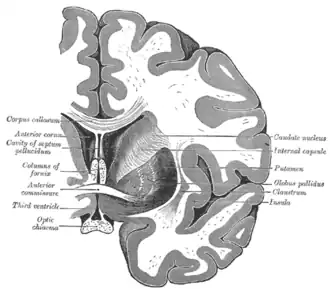

![]() Caudate nucleus (in red) shown within the brain | |

Structure

Along with the putamen, the caudate forms the dorsal striatum, which is considered a single functional structure; anatomically, it is separated by a large white-matter tract, the internal capsule, so it is sometimes also described as two structures—the medial dorsal striatum (the caudate) and the lateral dorsal striatum (the putamen). In this vein, the two are functionally distinct not because of structural differences, but merely because of the topographical distribution of function.

The caudate nuclei are near the center of the brain, sitting astride the thalamus. There is a caudate nucleus in each hemisphere of the brain. Each nucleus is C-shaped, with a wider "head" (caput in Latin) at the front, tapering to a "body" (corpus) and a "tail" (cauda). Sometimes a part of the caudate nucleus is called the "knee" (genu).[6] The caudate head receives its blood supply from the lenticulostriate artery; the tail of the caudate receives its blood supply from the anterior choroidal artery.[7]

The head and body of the caudate nucleus form part of the floor of the anterior horn of the lateral ventricle. The body travels briefly towards the back of the head; the tail then curves back toward the anterior, forming the roof of the inferior horn of the lateral ventricle. This means that a coronal section (on a plane parallel to the face) that cuts through the tail will also cross the body and head of the caudate nucleus.